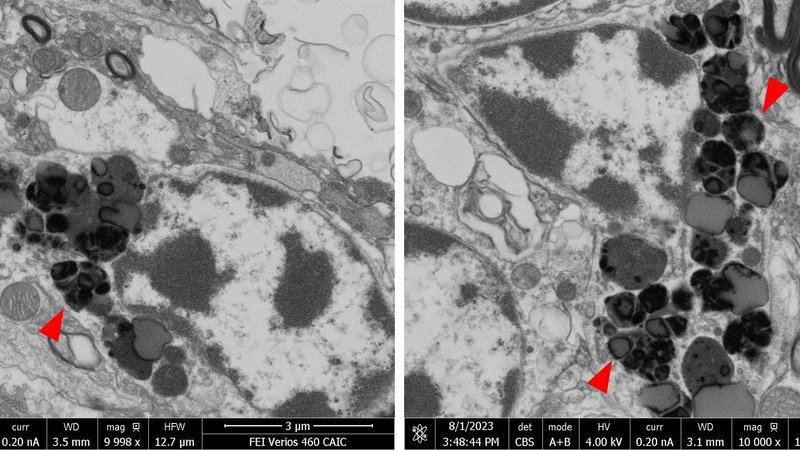

Formalin-fixed tissue was subsequently submitted to CAIC for EM analysis. SEM blockface imaging was able to quickly localize granular deposits even in large tissue sections. Electron-dense lipofuscin granules of varying sizes were found along with lipid droplets and electron-lucent material. The electron microscopic findings supported a diagnosis of neuronal ceroid lipofuscinosis (NCL).

Electron-dense lipofuscin granules in dog brain imaged by SEM blockface imaging (CAIC).

Genetic testing did not identify the causative genetic mutations usually associated with early-onset NCL in this dog breed. This case could therefore present a novel subtype of NCL, due to so far unidentified genetic mutation(s), leading to the onset of clinical symptoms only in adult life.